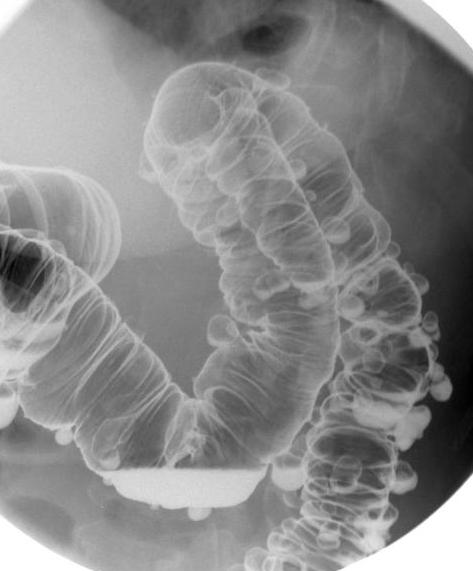

Diverticulose colique : Les

diverticules a difference taille s'etendue le long

du colon sigmoide , colon descendant et colon

transverse ( fleche rouge ) Image en spastique du

colon sigmoide ( fleche jaune ) peu se voyait

nettete . Image lavemevt baryte mono de contrast . |